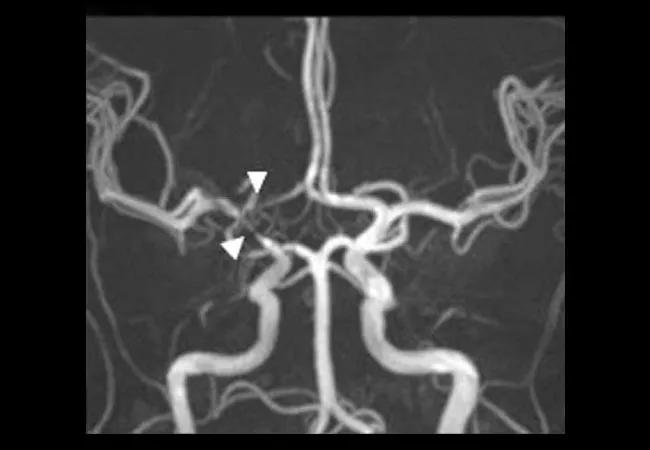

High-resolution vessel wall MRI (HR-MRI) adds diagnostic value by showing distinguishing vessel wall patterns for CNS-V and other, noninflammatory diseases (e.g., reversible cerebral vasoconstriction syndromes). With HR-MRI, one can visualize the wall of large and medium intracranial vessels and may be able to distinguish between disparate vascular diseases with similar angiographic findings. HR-MRI has become part of imaging protocols detecting causes of ischemic stroke, mainly in a research setting but increasingly asked for (and used) in clinical practice; its precise role and added value for prognosis and patient care needs further elucidation.

Representative postgadolinium contrast high-resolution MRI vessel wall image (a, d, g), 3D-TOF magnetic resonance

angiography (b, e, h), and contrast computed tomographic angiography (c, f, i) in patients with intracranial vasculopathy. (a, b, c) A 49-year-old female with central nervous system vasculitis. (a) T1-weighted arterial wall coronal image of the right terminal ICA and proximal A1 with strong smooth, concentric wall enhancement and thickening (arrows). (b) Magnetic resonance angiography revealed severe narrowing at the junction of the right terminal ICA, MCA, and ACA origin (arrow heads). (c) No evidence of intracranial ICA calcification. (d, e, f) A 47-year-old female with intracranial atherosclerotic disease. (d) T1-weighted arterial wall sagittal image showed mild wall thickening with eccentric wall enhancement at the left M1 segment (arrow). (e) Severe short segment stenosis was present at the origin of left MCA (arrow head). (f) Spotty calcification can be observed in the left intracranial ICA lumen (diamond arrow). (g, h, i) A 30-year-old female with reversible cerebral vasoconstriction syndromes. (g) T1-weighted arterial wall coronal image showed uniform wall thickening and wall narrowing without enhancement in the right M1 segment. (h) Magnetic resonance angiography revealed the mild to moderate narrowing in the proximal right MCA and the distal right ACA (arrow heads). (i) Intracranial ICA calcification was not present. 3D-TOF, 3D time of flight; ICA, intracranial artery; MCA, middle cerebral artery; ACA, anterior cerebral artery.